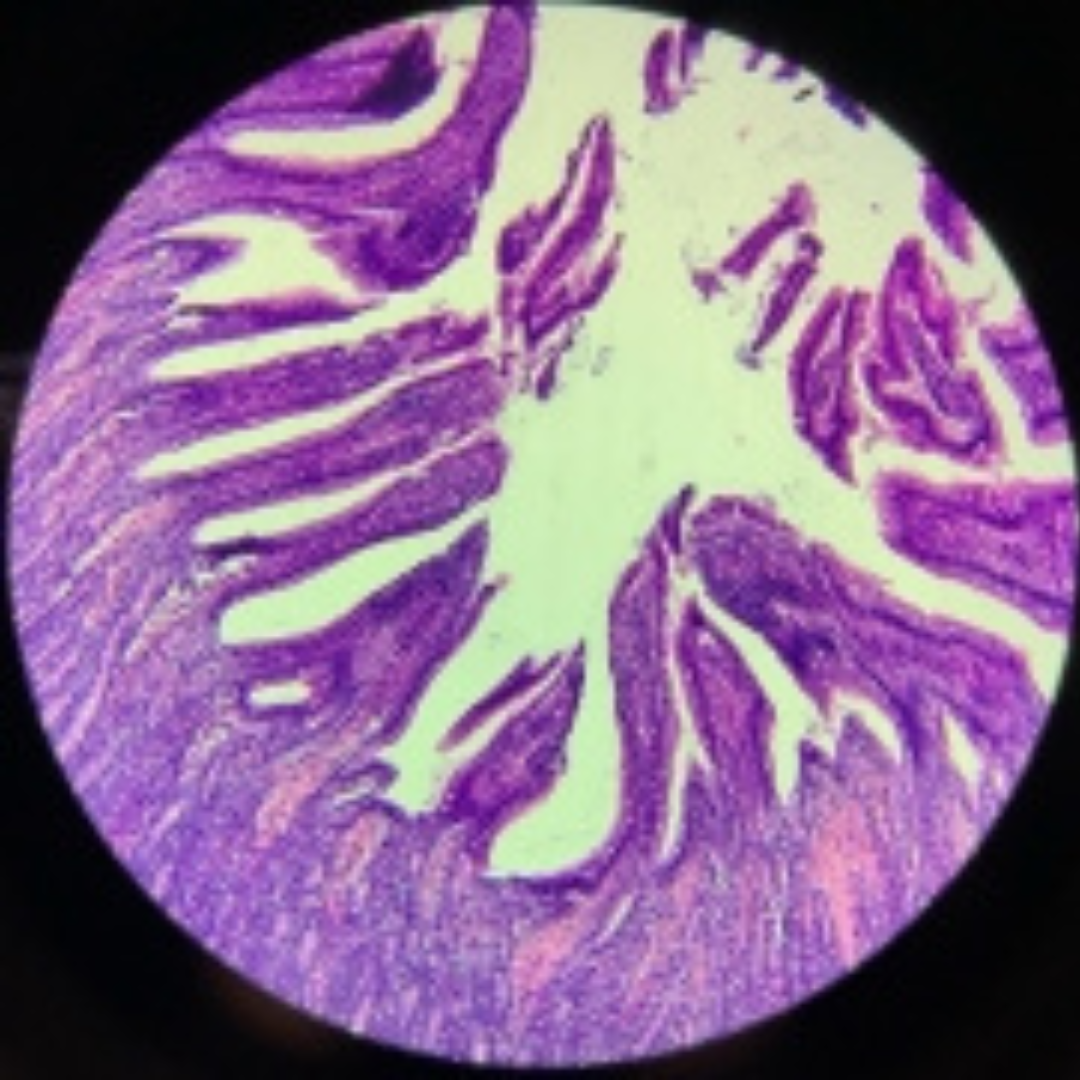

Elastic Arteries (Aorta)

Elastic Arteries (Aorta)

Elastic Arteries (Aorta)